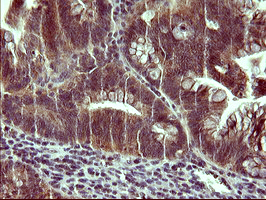

Immunohistochemical staining of paraffin-embedded Adenocarcinoma of Human colon tissue using anti-SNCA mouse monoclonal antibody. (MA00215) (1:150).